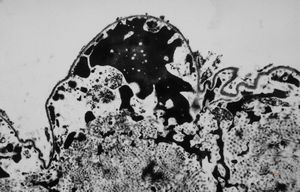

M,71y. | CADASIL accompanied with Alzheimer disease - brain vessel - arrows: granular osmiophilic material (GOM) between basement membranes

M,71y. | CADASIL accompanied with Alzheimer disease - brain vessel - arrow: granular osmiophilic material (GOM) in basement membrane